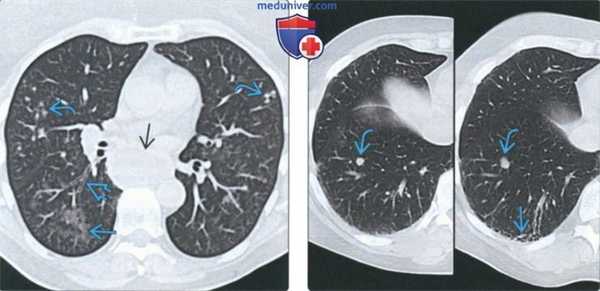

(Слева) На аксиальной КТ без КУ у пациента с прогрессирующим системным склерозом и аспирационным бронхиолитом визуализируются участки «матового стекла» и сгруппированные центрилобулярные очаги, а также минимально выраженные бронхоэктазы с обеих сторон. Определяется также расширение пищевода.

(Справа) На аксиальных изображениях (КТ) у пациента с прогрессирующим системным склерозом и аденокарциномой легкого продемонстрирован рост очага нижней доли правого легкого в течение 12 месяцев. В субплевральных отделах визуализируются фиброзные тяжи. У пациентов с интерстициальным заболеванием легких повышен риск рака легкого.